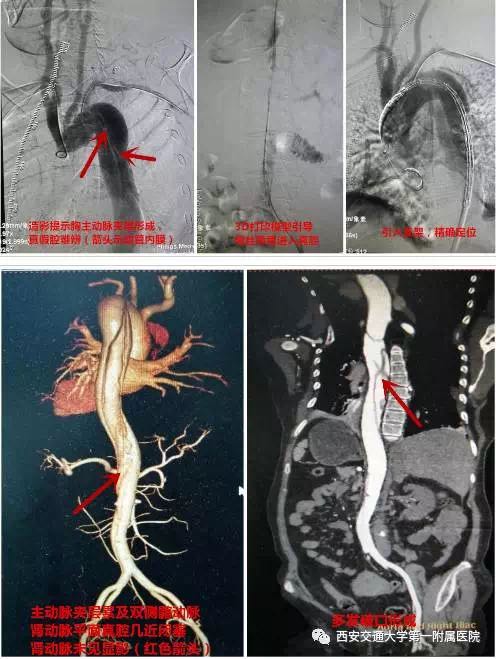

入院后行CTA检查提示主动脉夹层Stanford B型,累及双侧髂动脉,多发破口,真假腔形成,且假腔扩张压迫真腔,导致真腔变窄,肾动脉水平腹主动脉真腔几近闭塞,双侧肾动脉无血供,这也是导致患者无尿、肾功能急性衰竭的原因。

患者入院后立即予以吸氧、镇痛、镇静、稳定血压、预防感染等治疗,缓解症状及防止病情进展。同时针对该复杂病变,立刻组织病案讨论,并创新性的提出利用3D打印技术,1:1复原病变主动脉,进一步明确动脉破口位置、大小及程度,并以此作为手术引导。血管外科蔡惠住院总医师积极协调,于最短的时间内取得主动脉3D打印模型。3D打印的胸腹主动脉模型完美呈现出所有病变的特点,并提示最佳的手术入路及真腔走形。随后,在介入手术室及血管外科护理团队的配合下,经过精心地术前准备,以娴熟的手术技巧,仅用半小时就顺利完成该例复杂胸主动脉夹层腔内修复术,术中即显示几近闭塞的真腔重新开放,一侧肾动脉重新恢复血流灌注。术后患者恢复良好,术后第2天即有排尿,且尿量进行性增加,至患者出院时,尿量已增加至500-600ml。